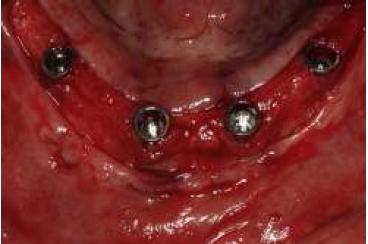

La planificación se realizó por medio de una ortopantomografía (fig. 5), evitando la utilización de cone-beam, siguiendo nuestro objetivo de realizar un tratamiento con un bajo costo. Al momento de la cirugía la paciente se encontraba premedicada con amoxicilina de 500 mg cada 8 h desde el día anterior15,16, ibuprofeno 400 mg cada 8 h10, comenzando 1 h antes de la cirugía17 y colutorios de clorhexidina al 0,12%, habiendo iniciado el tratamiento 48 h antes del procedimiento quirúrgico4. En el pabellón se probó nuevamente la guía multifuncional en boca (fig. 6), se anestesió a la paciente para luego realizar una incisión crestal desde la zona del primer molar derecho a la zona del primer molar izquierdo10,15,18, con incisiones liberadoras bilaterales, para luego realizar la disección subperióstica lingual y vestibular18. Con la plantilla radiográfica proporcionada por el fabricante se seleccionó sobre la radiografía panorámica el largo de los implantes a colocar. La cantidad de tejido óseo en sentido vestíbulo-lingual observada durante la cirugía fue de 5-6 mm, por lo que los implantes utilizados fueron implantes cónicos Strong SW de hexágono interno (SIN®, Sao Paulo, Brasil) de 3,8 mm de diámetro. Con la ayuda de la guía como referencia, se colocó 2 implantes distales, uno en cada lado, en la zona de los primeros premolares, inclinados a distal5, teniendo una longitud de 13 mm. Otros 2 implantes se colocaron a cada lado de la línea media mandibular, con una longitud de 15 mm. Se comprobó que los 4 implantes tuviesen una estabilidad primaria superior a los 30 N/cm (fig. 7). Se instalaron pilares Mini-Abutment y cilindros de protección de pilar, también teniendo como referencia la guía multifuncional. Se eligió suturar los tejidos con sutura no reabsorbible 4-018,19 (Seda, Ethicon, Johnson & Johnson, Brasil), siguiendo nuestro objetivo de disminuir los costos del procedimiento, y se envió a la paciente a la sala de recuperación (fig. 8).